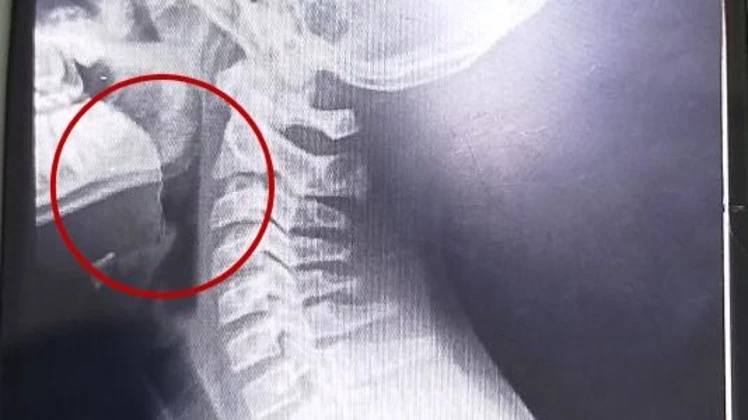

Pero lo más impactante se conoció tras los estudios por imágenes: en las placas detectaron un objeto extraño alojado en la vía aérea superior.

Tras una interconsulta con el servicio de otorrinolaringología, se decidió su ingreso urgente a quirófano. Allí, los médicos se encontraron con lo inesperado: un alambre fino incrustado en la garganta del chico.